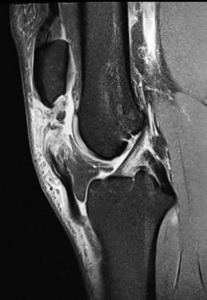

Patellar tendon rupture is a devastating injury and occurs in approximately one per 100,000 knees (for any reason). (Figure 1) Following primary total knee arthroplasty (TKA), patellar tendon rupture approaches an incidence of 2.5%, and > 5.0% following revision TKA (Vaishya et al. 2016).

Generally, a patellar tendon rupture is classified by the time from injury. Acute ruptures are treated less than six weeks s/p injury:

Chronic ruptures involve those that occurred at least two or three months and longer. These are the most difficult since: